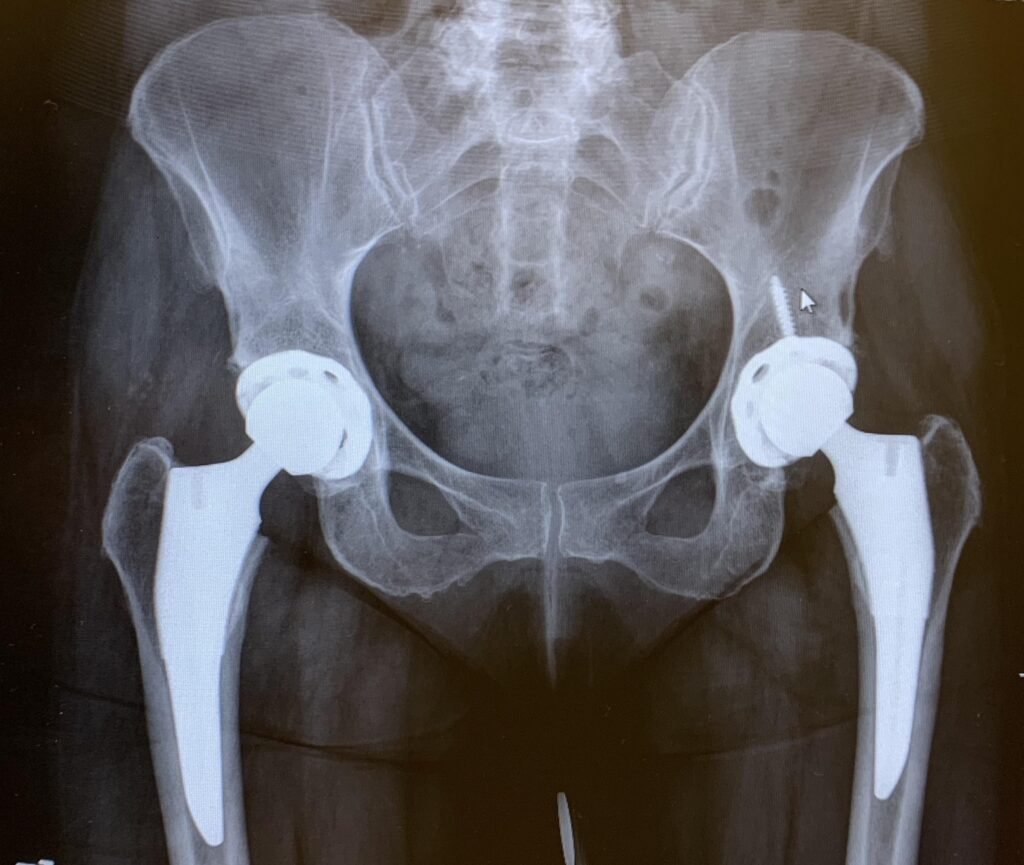

Bilateral Total Hip Replacement

When arthritis or joint damage affects both hips, it can significantly impact your ability to walk, sleep, and complete daily tasks. In these situations, bilateral, (double)  total hip replacement, where both hips are replaced, may be considered to help restore mobility and quality of life.

Bilateral hip replacement refers to replacing both hip joints with prosthetic implants. This can be done:

The goal of bilateral hip replacement is to reduce pain, improve balance and mobility, and help patients regain independence when both hips are affected by advanced arthritis or damage.